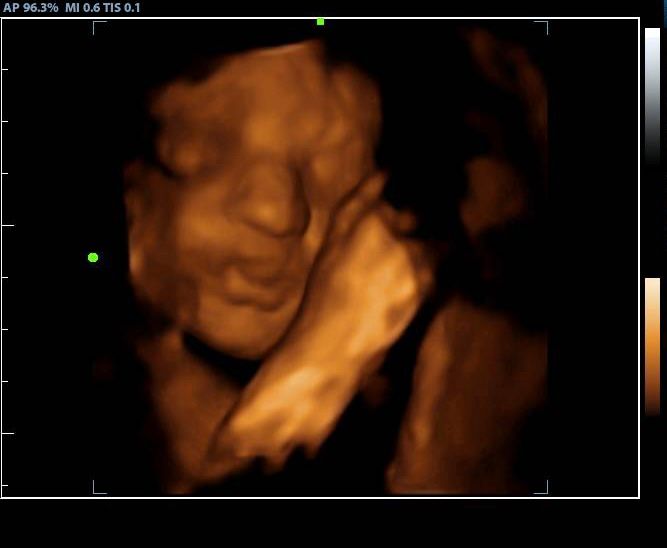

2d, 3d,4d & HD live

We bring the joy of seeing your baby right to you with our private, in-home ultrasound services. We also offer placenta encapsulation for those who choose it.

Family and friends are welcome to join the experience — whether in your living room, a cozy bedroom, or even at a relative’s home. With endless options and a deeply personal touch, we make your ultrasound session as special and unforgettable as the moment itself.

Enjoy a private, affordable ultrasound from the comfort of your home, perfect for moms between 7–41 weeks. Share the moment with loved ones by connecting directly to your TV for real-time viewing in 2D, 3D, or 4D. Ideal for baby showers or gender reveal parties!